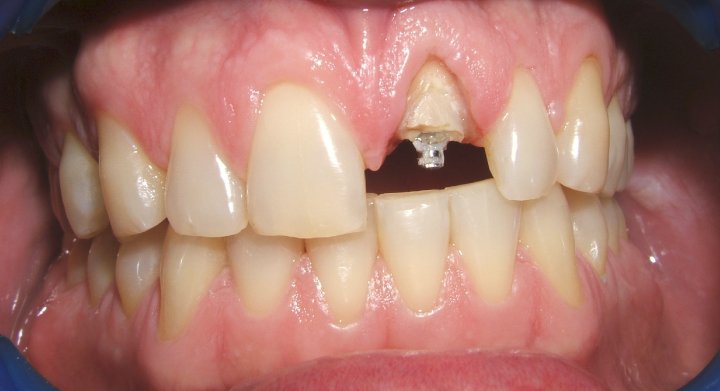

Fractured Tooth

Removal Of Tooth